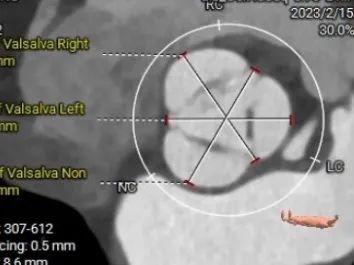

术前动脉CT评估:患者主动脉瓣三叶式,瓣叶无钙化增厚,冠脉开口高度可,双侧髂总动脉可见局限性溃疡,左侧溃疡更重,双侧髂外动脉内径偏细。

术前CT评估

瓣环:28.1mm

瓣上2mm:26.1mm

瓣上4mm: 23.6mm

STJ

LVOT:26.5mm

升主动脉大小:37.1mm

右冠高度:14.5mm

左冠高度:12.2mm

主动脉-心室角度

舒张期环直径:30.4